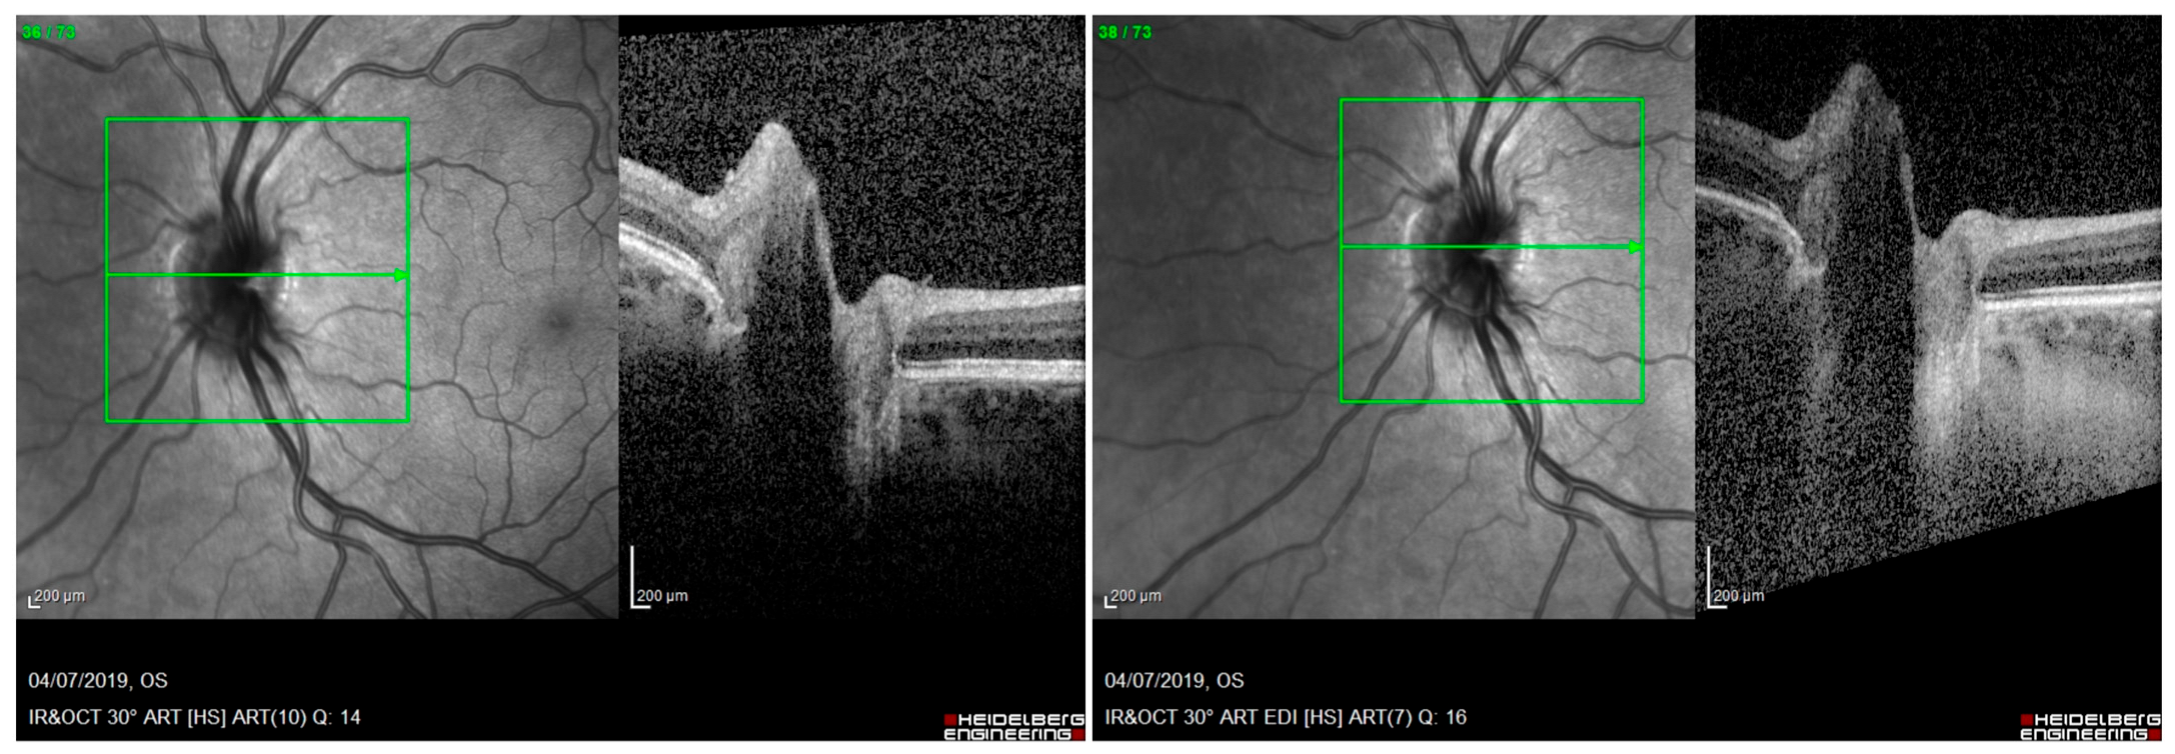

- We apologize for the misunderstanding. Figures 3 and 4 do not represent enhanced depth imaging (EDI) OCT acquisition of optic disc drusen (ODD) and peripapillary hyperreflective ovoid mass-like structures (PHOMSs). The purpose of those images was only to represent how they appear in OCT scans, and they were not used for testing OCT sensitivity to detect ODDs and PHOMSs. In our study we acquired both EDI and non-EDI images to recognize both ODDs and PHOMSs, as shown in Figure 1 and Figure 2, but only EDI images were analyzed according to ODDs consortium protocols [3]. Following the example of other similar studies [4], we decided to publish non-EDI figures, but we forgot to highlight that the selected images were not in EDI. However, to avoid misunderstandings, a detailed description of the acquiring protocols of OCT images could be useful.